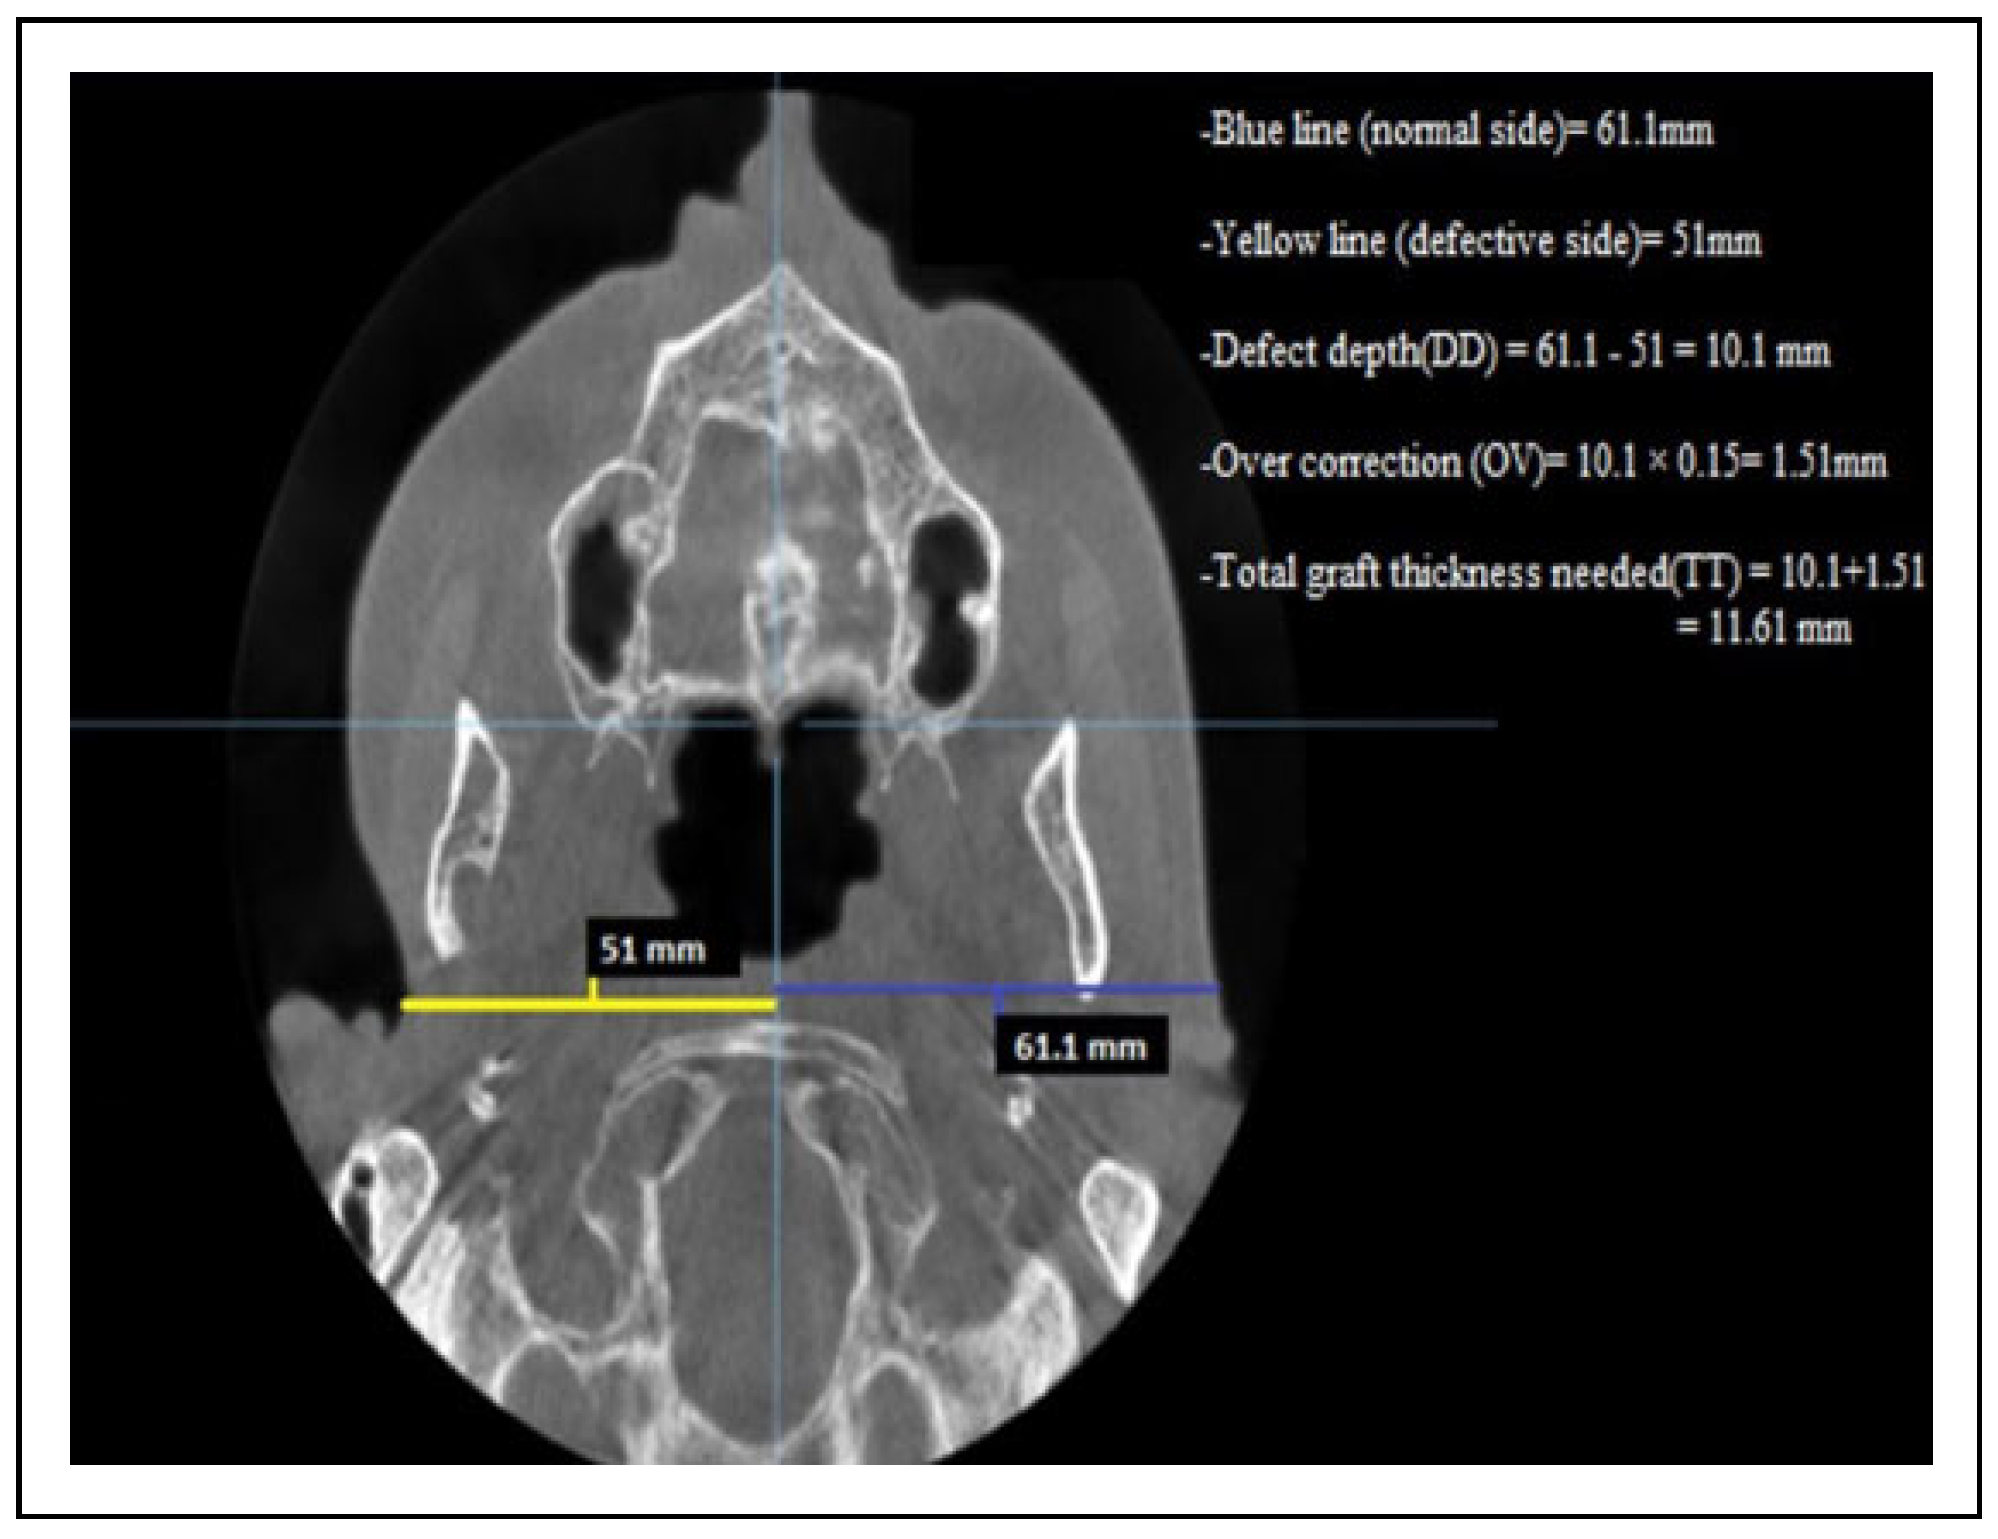

- The measurement of the defect’s depth (DD)Through axial section, a reference point was determined and each half of patient’s face was measured with a linear measurement. The measurements started in the defect side from the deepest point of the soft tissue defect into the midline.The unaffected or normal side was measured at the same horizontal plane with the opposite side from the most lateral soft tissue point into the midline. The difference between these 2 sides represents the defect’s depth (DD).

- Determination of overcorrection in a numeric value (OV)In our study, the overcorrection percentage is 10%-15% from defect’s depth. The defect’s depth (DD) was multiplied by 0.15 to convert the percentage of overcorrection into a numeric value.

- Determination of total graft thickness (TT).The total graft thickness that was needed for each patient was determined by the following formula:Total graft thickness(TT) = defect’s depth(DD) + overcorrection numeric value(OV).The evaluation of patient’s improvements was done through 2 methods: